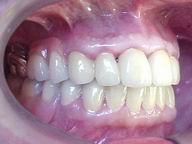

Reabilitação funcional e estética em ambas as arcadas

com próteses fixas e removíveis de encaixe de precisão.

DEPOIS